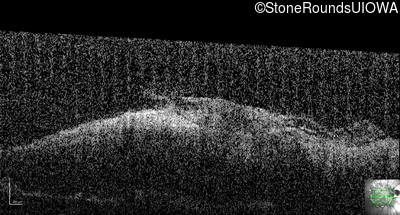

This 9 year old male was noted to have some crossing of his eyes at 2 months of age and the eye exam which followed identified a retinal lesion in the right eye. When he was six years old an epiretinal membrane was noted in his left eye. Two years later it was decided that it was a thin hamartoma in that eye as well. He underwent neuroimaging at age 7 which identified bilateral acoustic neuromas.

| Age at visit: 8 years |

| Age at visit: 10 years |